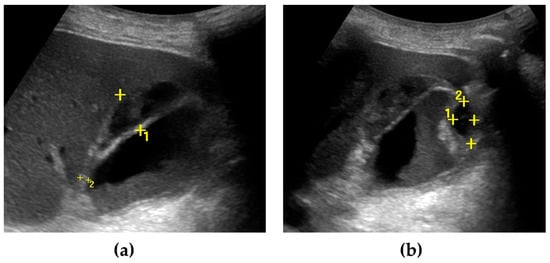

4.3. Imaging Findings

- Mencarini, L.; Vestito, A.; Zagari, R.M.; Montagnani, M. New Developments in the Ultrasonography Diagnosis of Gallbladder Diseases. Gastroenterol. Insights 2024, 15, 42–68. [Google Scholar] [CrossRef]